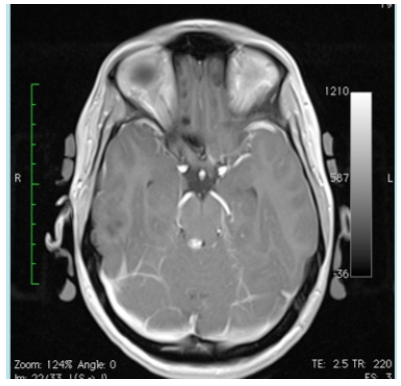

The mother and grandmother had also frequent nosebleeds with the presence of telangiectesia at the levels of the lips, tong, fingers and stomach. These findings were absent in our presented patient. The magnetic resonance (MR) angiography of the brain showed no arteriovenous malformations (Figure 1). On MR imaging a small bleed was observed in the right superior colliculus at the level of the mesencephalon (Figure 2). Also a small bleed was detected in the left anterior paramedian part of the pons (Figure 3).

Figure 3 Magnetic resonance imaging of a horizontal section of the pons and cerebellum. A small bleed is present the left paramedian anterior region of the brainstem.

The small bleed in the pons was most probably responsible for the transient diplopia of this patient. On the other hand the small lesion in the mesencephalon was asymptomatic. Asymptomatic strokes occur frequently in HHT.8 The small cerebral lesions are most probable due to embolic strokes, issued from non-detectible pulmonary shunts.9 MRI of the brain with additional spectroscopy allows the distinction between cerebrovascular lesions and brain abscesses.10 The diagnosis of HHT is associated with a significant poor survival rate.11